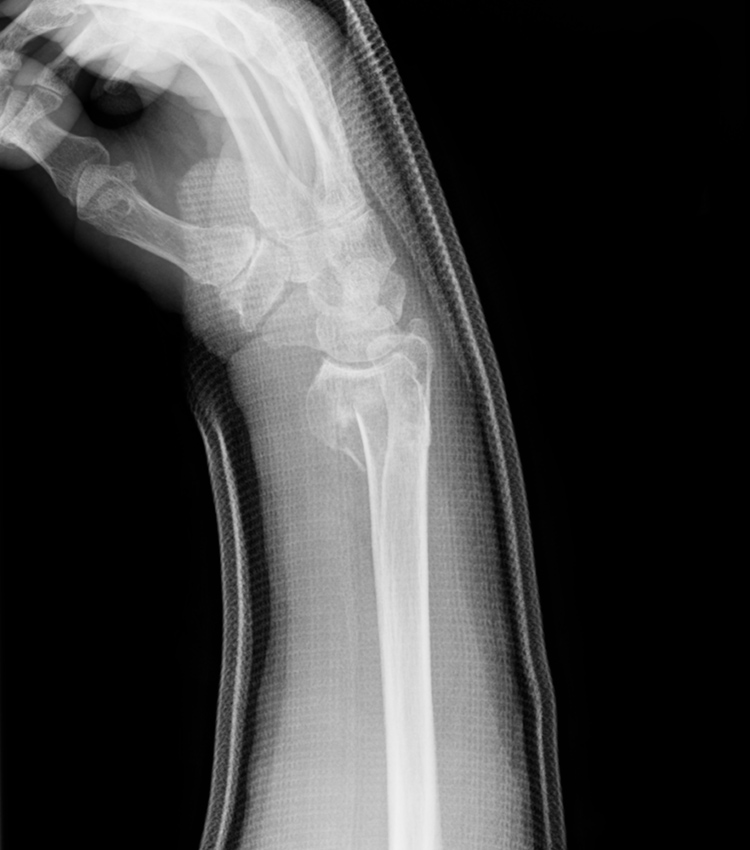

橈骨遠位端骨折

転倒して手をつくことで起こる手首の骨折です。北海道では雪道で滑ることで発生するため冬の期間に多く起こります。まずは痛いのですが、徐々に腫れが出てきます。ズレが大きい場合には手首に変形が見られます。

レントゲンで骨折の状態を確認します。ズレ(転位)が少ない時にはギプスなどの外固定で治りますが、転位が大きく整復してもまたズレてしまう時には手術をお勧めしています(骨接合術)。手術では直視下に骨折を元の位置に戻し専用のチタン製の金属で固定します。その金属は原則として外す必要はありません。